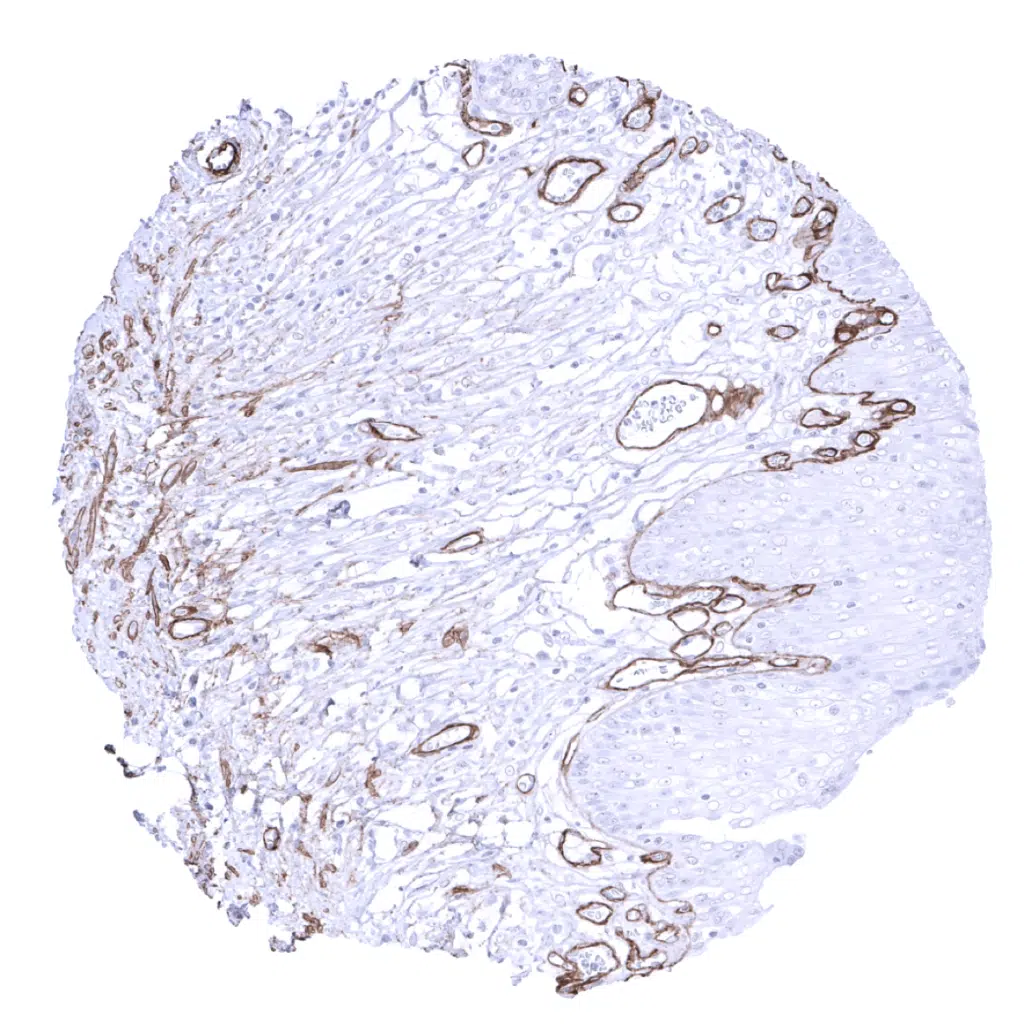

Prostate - In the prostate, smooth muscle cells are surrounded by collagen IV. Basement membranes and vessels are also staining.